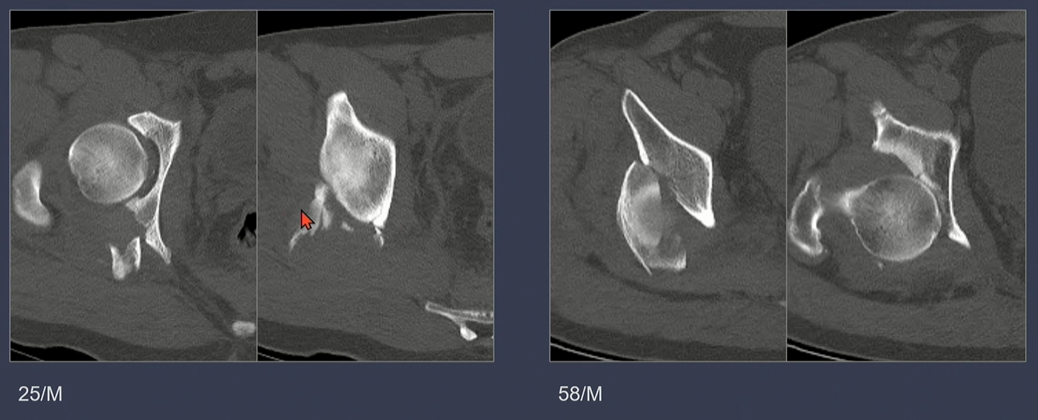

displacement가 없는 경우.

displacement가 있는 경우